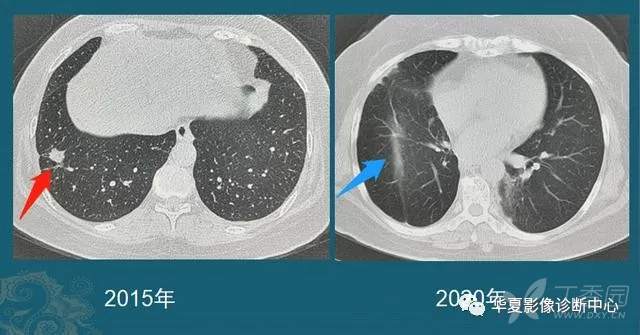

我们每年都能发现很多从肺小结节长大的肺癌,挑出两个速度最快的分享一下:

这位病人2016年体检还是正常的,2017年查出一个3mm的肺结节,用了两年半时间,增长到>1cm,手术病理是肺腺癌。

注意:这几乎是最快的一类的,很少见!所以高危人群推荐每年胸部体检一次是有益的。